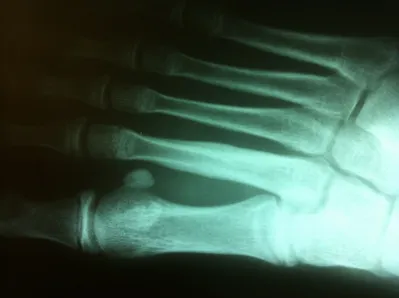

Diaphysial stress fractures of the fifth metatarsal are more uncommon. These fractures are in an area of the fifth metatarsal bone that has a very poor blood supply. These fractures are often treated with eight weeks nonweightbearing. In rare cases, the fracture does not heal and it may require a small screw to be placed through the bone to allow the fracture to heal. In athletes that do a lot of running or those who have a foot that has a slight turning in of the front part relative to the back part of the foot, surgery may be indicated earlier due to the high propensity for refracture following healing of the primary fracture.

Stress fractures of the metatarsal are also more frequent in some patients that have long metatarsals. Treatment for these stress fractures is often just the use of a boot to unload the metatarsal during the healing process. This would be followed by an orthotic to be placed in the shoe to rebalance the weight-bearing distribution of the metatarsal heads. Long-term prognosis is usually excellent. Rarely do stress fractures fail to heal. Rarely is surgery necessary for these injuries